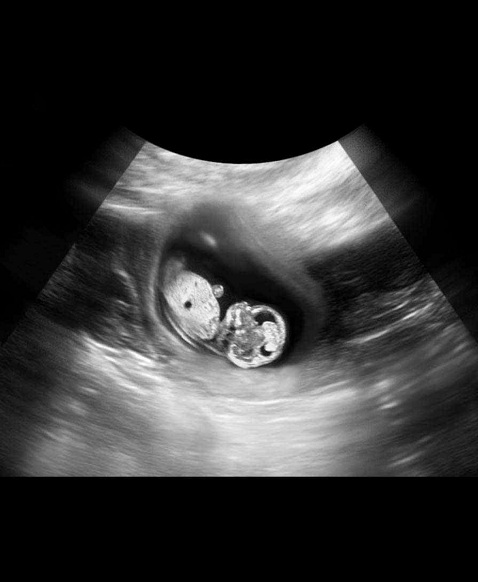

B超图

胎儿发育

本周已能够清晰地看到胎儿脊柱的轮廓,脊神经开始生长。你的子宫现在看起来象个柚子,借助多普勒仪器,你可以听到胎儿心脏快速跳动的声音,有些孕妇称之为快速奔跑的小马。